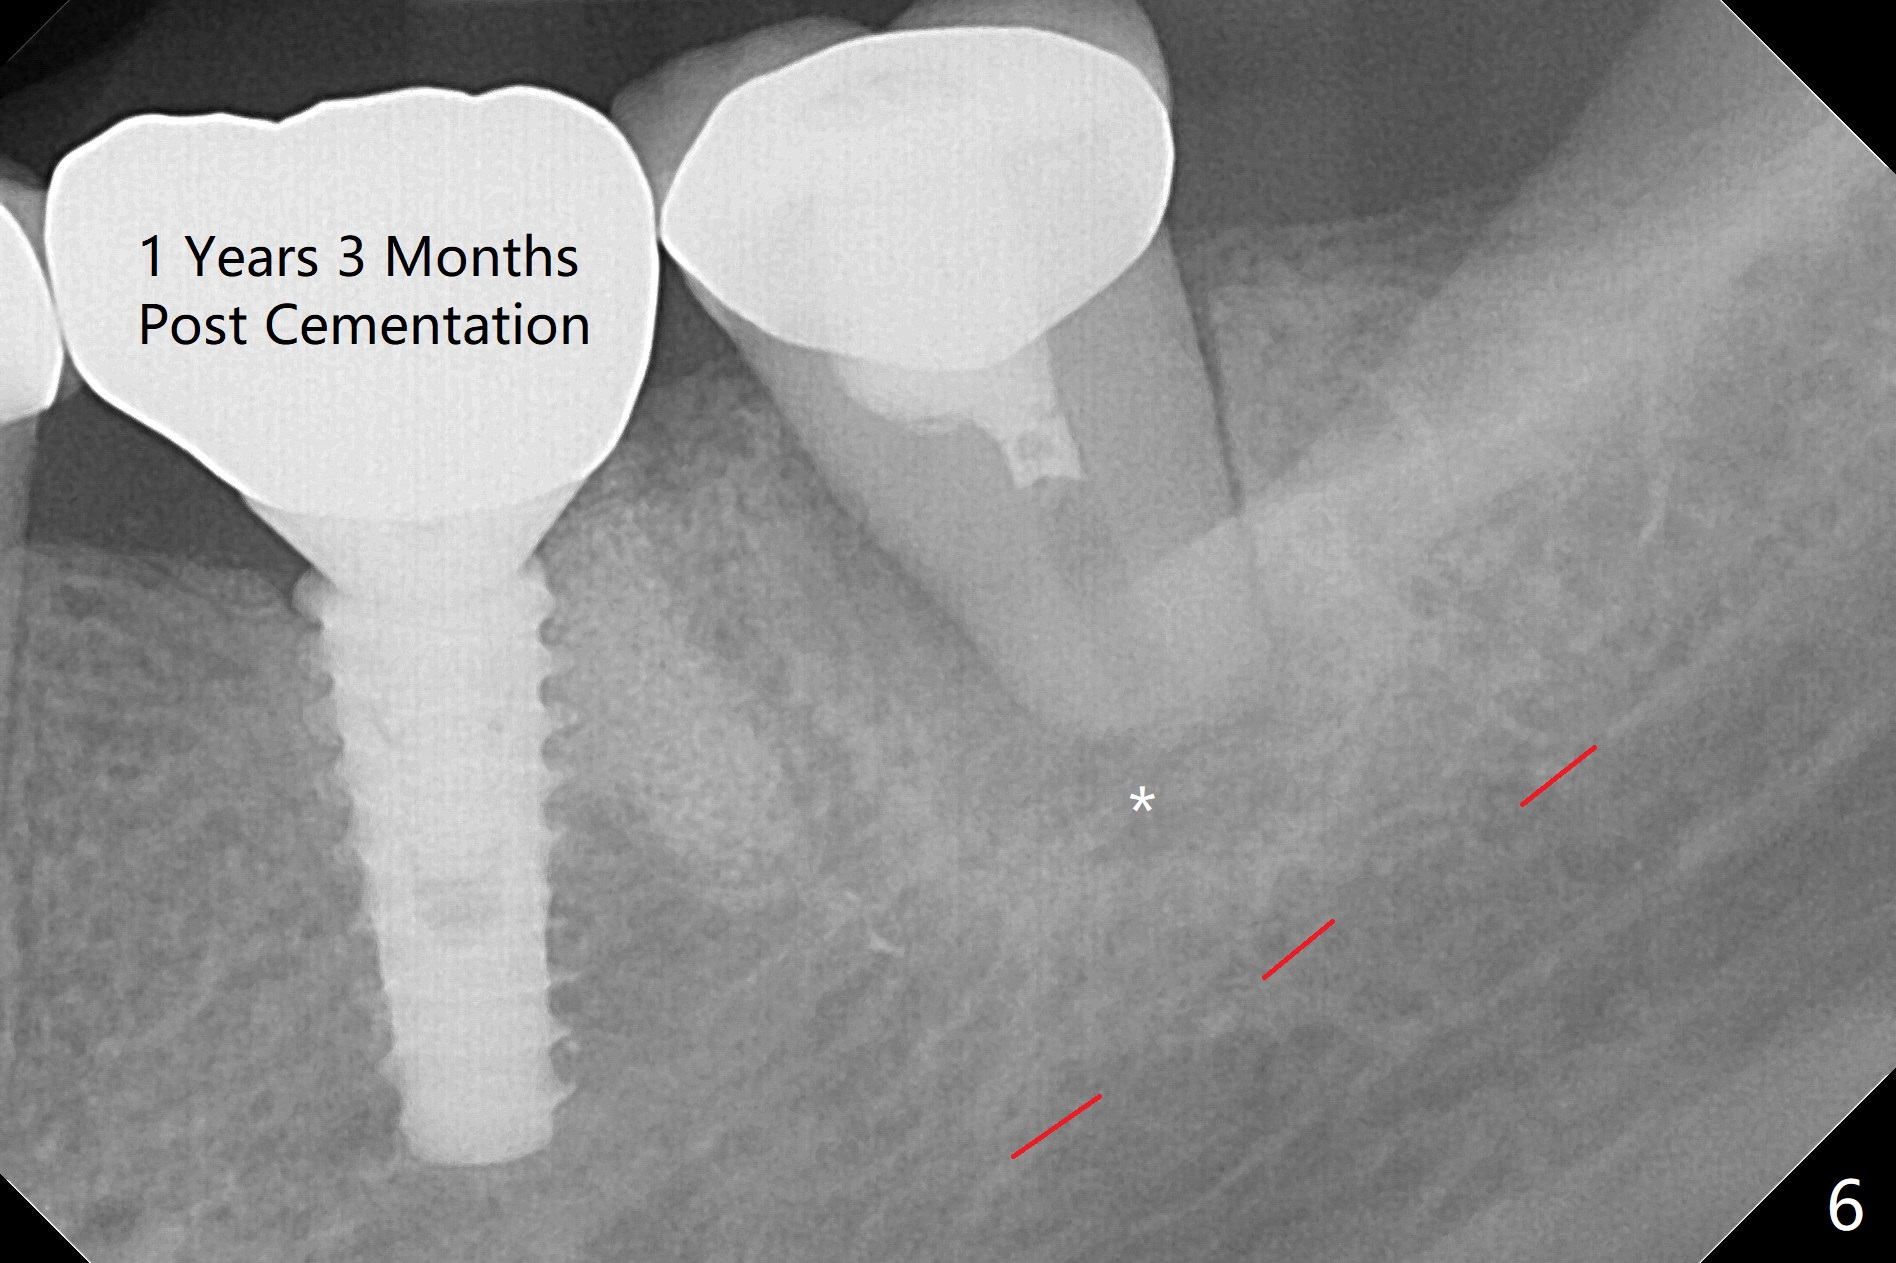

After making a 10 mm incision at the site of #19, #15c blade is used as an osteotome to start bone expansion, followed by Magic Split and Magic Expander (ME, 3 mm in diameter).  The depth is approximately the bottom of the mesial socket.  The osteotomy beyond the socket has to be done with 1.6 mm pilot drill (Fig.1) in combination of ME.  Following ME 4.3 mm and Magic Drill (MD) 3.8 mm for 15 mm (gingival level), a 4.5x11 mm dummy implant is placed with 50 Ncm (Fig.3); the implant looks narrow for the edentulous space.  After ME 4.8, MD 4.3 for 13 mm and Final Drill for 15 mm, a 5x11 mm IBS is inserted with >50 Ncm (Fig.3).  With 2 more turns of the implant, a 6.5x4(2) mm abutment is placed (Fig.4).  Periodontal dressing is applied around the abutment for additional retention.  A provisional is fabricated 3 weeks postop.  The provisional and abutment are loose 4 months postop (Fig.5).  After retightening the abutment, impression is taken for final restoration.  There is no bone loss 1 year 3 months post cementation (Fig.6).  After use of #100 file (Fig.7), the canal is debrided with #140 file with 1.5 mm shorter in working length with placement of Calcium Hydroxide paste.  Pain gets worse post RCT retreatment. There is limited native bone for primary stability when an immediate implant is placed (red dashed line: the superior border of the Inferior Alveolar Canal).  Prepare IS regular and extra wide kits and tissue-level implants (>5 mm).  Socket preservation may be done instead.  If the socket is large and the vein is not so small, prepare PRF.  In fact blood drawing fails.  When the tooth is extracted, it is sensitive to remove granulation tissue.  Socket preservation is done with Vanilla graft at #18 (Fig.8); there is ~3.5 mm bone between the bottom of the single socket and the Inferior Alveolar Canal (red dashed line).  The socket at #18 seems to have healed 4 months post extraction (Fig.19), but the bone height appears to have been reduced (compare Fig.10,11).  The buccolingual width is also decreased (Fig.12,13).  A 4.5 or 5.0x10 mm implant is appropriate for the site (Fig.14).  There is no bone loss at #19 (which may be associated with the bone expansion) 1.5 years post cementation (Fig.15).  Therefore the osteotomy at #18 will be assisted with bone expanders after 2.2 mm drill.